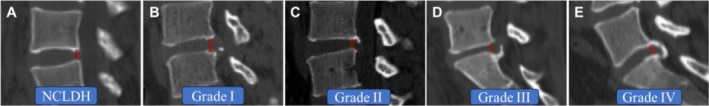

Methods: A total of 271 patients who suffered from single CLDH (97 patients) or NCLDH (non-calcified lumbar disc herniation) who received PEID surgery between January 2016 and December 2018 in our hospital participated in this retrospective study. Moreover, CLDH was divided into four grades based on preoperative sagittal CT images, including 34 Grade I, 22 Grade II, 19 Grade III, and 22 Grade IV. Operative time was evaluated between the two groups. In addition, VAS (leg pain), ODI, and MacNab scale score were applied to assess the efficacy of PEID in treating CLDH with different calcification degrees by Student's t tests or χ2 test.

Conclusion: CLDH was innovatively divided into four grades in our study. PEID is an effective and safe surgical method for treating CLDH; it can achieve a satisfactory outcome. However, it should be considered carefully in the treatment of lumbar disc herniation with severe calcification (Grade IV).